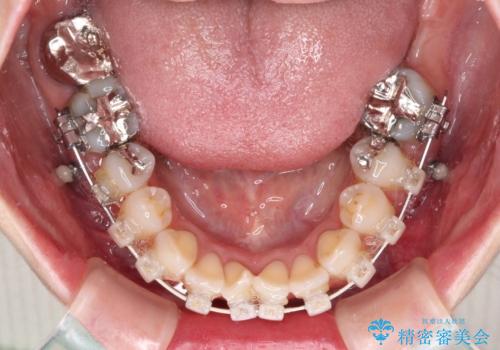

インプラント部は治癒待ちの期間が長くなるため、その期間を利用して下顎の叢生を解消し、より理想的な咬み合わせで補綴治療を行うこととしました。

下顎前歯の歯列を整えたことで、上顎前歯の咬み合わせが安定し、自然な口元に仕上げることができました。